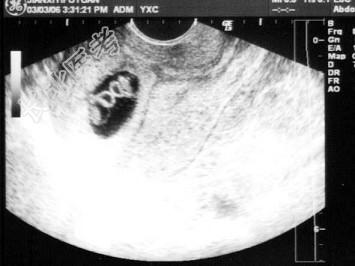

- 单项选择题女,25岁, 停经50天,B超检查如图所示, 以下最可能的诊断为   (   )

A、早孕(双胎)

B、葡萄胎

C、宫腔积血

D、早孕(单胎)

E、以上都不是